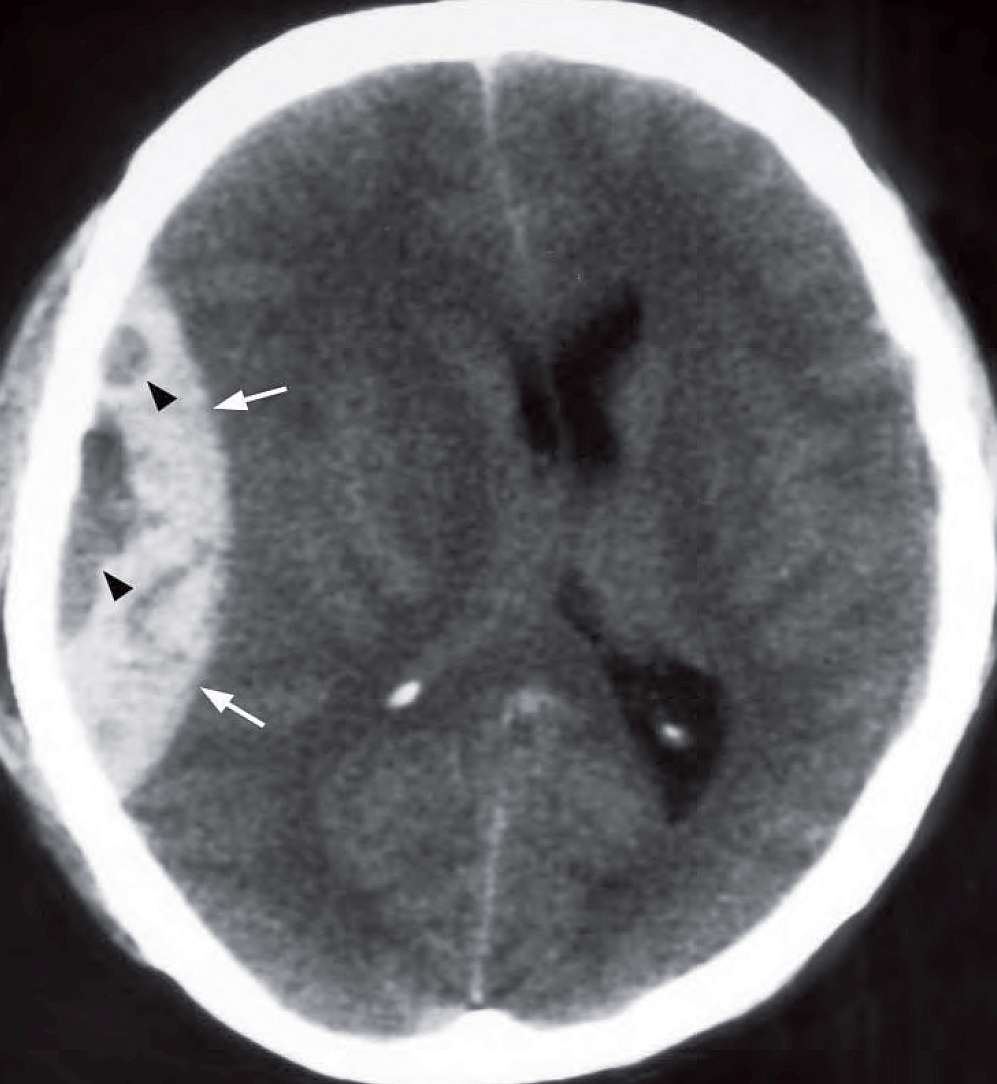

Extra-axial blood in the right temporoparietal area, heterogeneous in density, biconvex in shape with mass effect causing cerebral and ventricular compression and midline shift to the left.

Non-contrast axial CT of the brain showing an acute right frontoparietal extradural haematoma (arrows) with mass effect on the underlying brain and lateral ventricles, midline shift to the left. The low density areas (arrowheads) within the extradural indicate active bleeding.

- Low density areas within the EDH indicate active bleeding and thus heterogeneity may predict rapid expansion of the haematoma